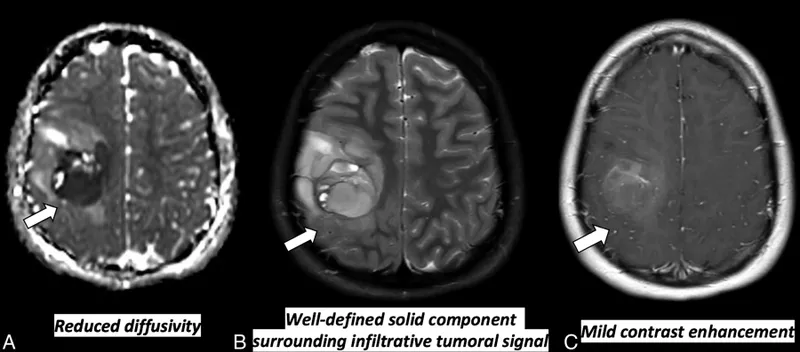

- Imaging reveals ring-enhancing lesions with significant vasogenic edema on contrast-enhanced CT/MRI.

- Appearance: Ring-enhancing lesions with significant vasogenic edema.

- Pathology: Often multiple, well-demarcated lesions at the gray-white junction. Histology mirrors the primary tumor (e.g., glands in lung adenocarcinoma, melanin in melanoma).

- Look for a distinct border between tumor cells and surrounding brain parenchyma, often with significant vasogenic edema.